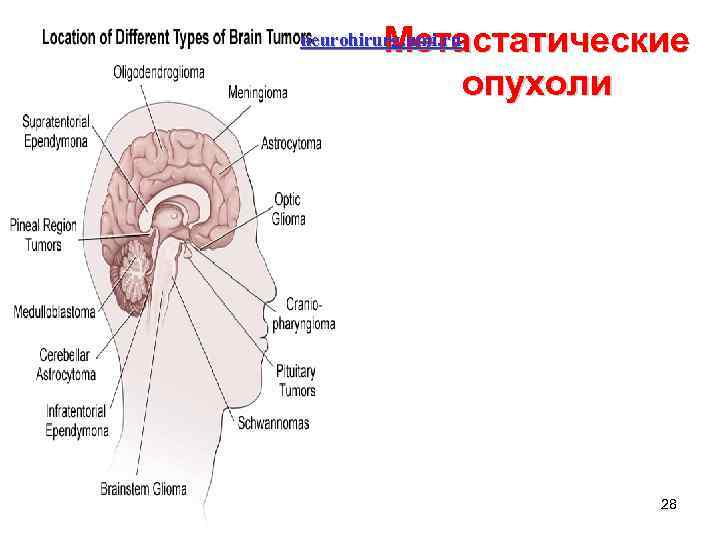

Метастатические опухоли neurohirurg. umi. ru 28